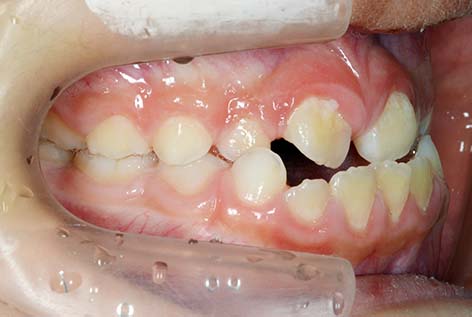

![]() |

⑧叢生(乱杭歯):歯が重なり合ったり、不規則に並んだりする状態を指します。 具体的には、歯がガチャガチャと生えているように見えることが特徴で、見た目の問題だけでなく、歯垢(プラーク)が貯まりやすくなり、むし歯や歯周病のリスクが高まります。主な原因は、歯のはえる場所(スペース)の広さと歯の大きさのアンバランスによります。 健診基準は、隣り合う歯が4分の1以上重なっていれば判定「2」とします。 |